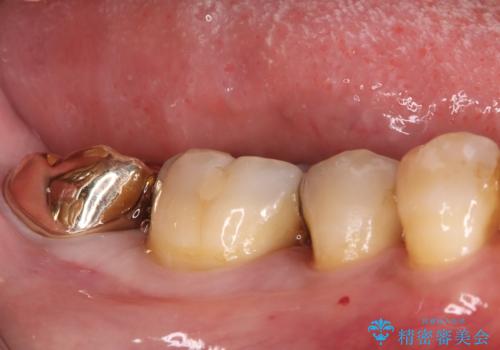

- 以前治療した右下7番(奥歯)のインレー(詰め物)が欠けてしまったことを主訴にご来院されました。診査の結果、残っている歯質が少なく、通常の詰め物では再び歯が割れてしまう破折リスクが高いと診断しました。このリスクを回避し、強い咬合力に耐えられるよう、歯全体を覆うクラウン(被せ物)による修復を提案。素材には、強度と適合性に優れたPGA(白金加金)クラウンを選択し、長期的に安定した奥歯の機能回復を目指しました。

治療ではまず、欠けた部分を修復し、歯全体を均一に形成しました。その後、PGA(白金加金)クラウンを作製・装着しました。